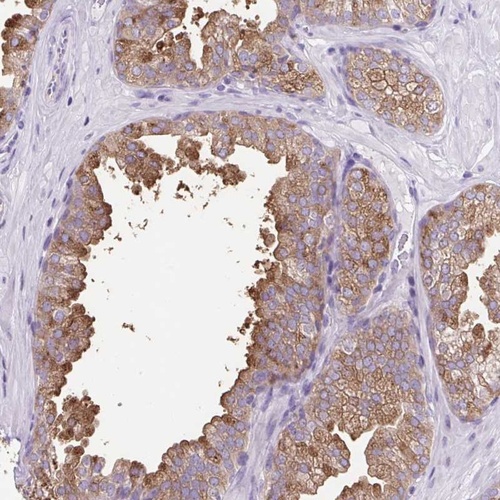

Immunohistochemical staining of human prostate shows moderate cytoplasmic positivity in glandular cells.